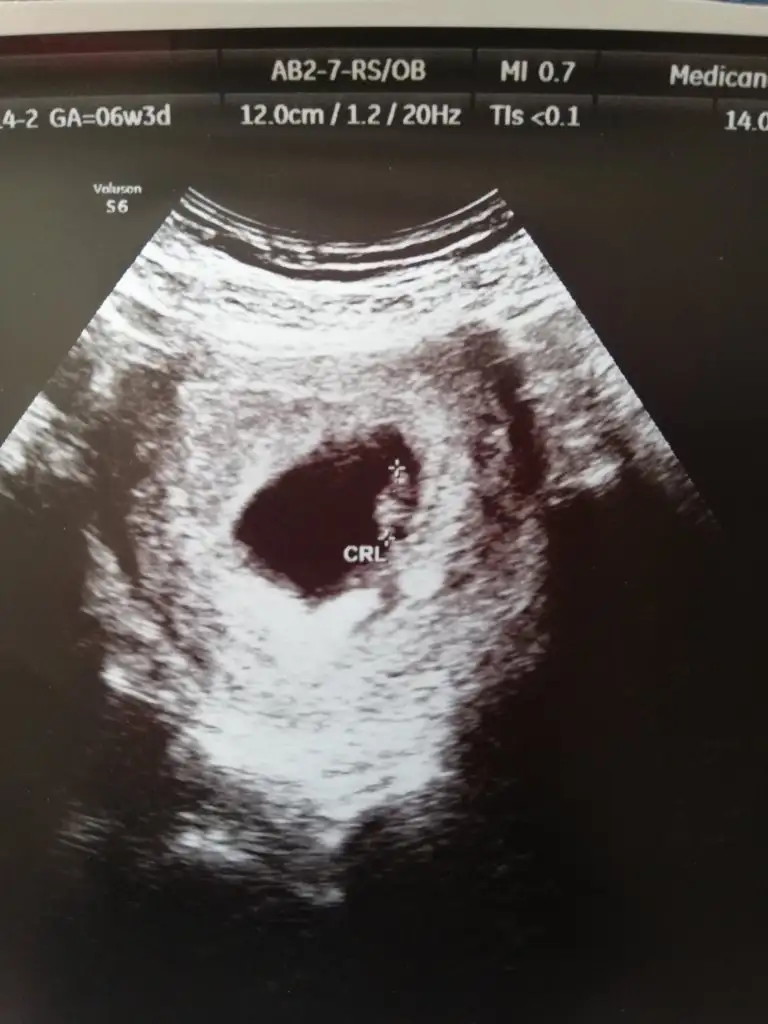

@dilek062 canım banada tahmin yaparmisin ? Bu karından ultrason görüntüsü 7+1 günlük..

Ben anlamadım ama bi arkadaş yorumlamıştı kız demişti bakalım tutar inşallahRamzi teorisine göre ( bilimsel bir araştırma sonucuymuş ve %85 doğruluğu varmış). İlk 6-8 haftalık ultrason görüntüsüne göre bebeğin kesenin içersinde soldan ya da sağdan girişine göre cinsiyet tahmini yapılıyor. Bilimsel olunca tecrübeli annelerimiz yada anne adaylarımızdan yardım istiyoruz. Doğruluğu var mı öğrenmek adına :) Bizleri aydınlatırsanız çok seviniriz. bu teorieye göre;

Vajinal muayeneyle bakıldıysa eğer;

Sağdan girmiş gözüküyosa aslında solmuş ve ERKEK,

Soldan girmiş gözüküyosa aslında sağmış ve KIZ ,

Karından bakıldıysa eğer,

Soldan girmiş gözüküyosa gerçektede solmuş ve ERKEK,

Sağdan girmiş gözüküyosa gerçekte de sağmış ve KIZ

Böyle bir yazı paylaşılmış belki tahmin edebilirsin canım